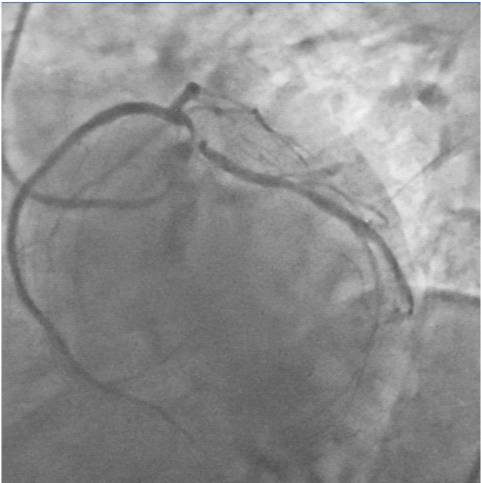

A check shot done at this stage of the procedure demonstrated fully expanded LM-LAD and LCX stents with brisk TIMI 3 flow into both arteries, but large fragments of thrombi appeared in the LAD artery (Figure 10), (Video 3) The patient complained of chest discomfort and this was accompanied with slight lowering of heart rate and drop in blood pressure. An intra-coronary (IC) bolus injection of tirofiban (20mcg/Kg) was immediately administered and this rapidly completely lysed the thrombi in the LAD artery (Figures 11 & 12), (Video 4). The patient was shifted to the CCU on intra-venous tirofiban infusion for the next 18 hours. His further stay in hospital was unremarkable, and he was discharged on the third day in stable condition on aspirin, prasugrel, atorvastatin, ramipril and metoprolol.

Figure 10 Check shot done after kissing balloon shows large burden of thrombi in LAD artery and no re-flow in distal artery, necessitating intracoronary high doses tirofiban administration ( 25mcg/Kg).